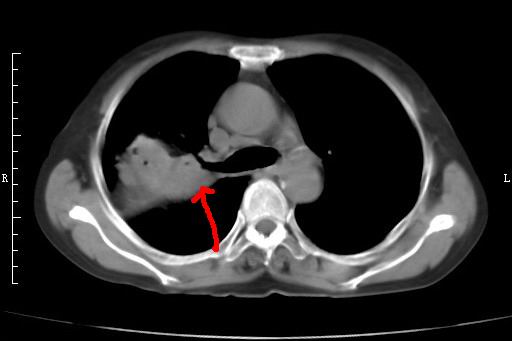

标题: CT27173:右上叶后段肺癌 [打印本页]

标题: CT27173:右上叶后段肺癌

右上叶后段肺癌伴阻塞性炎症(肺脓肿形成)

支持楼主【气管腔狭窄定性癌肿意义大】